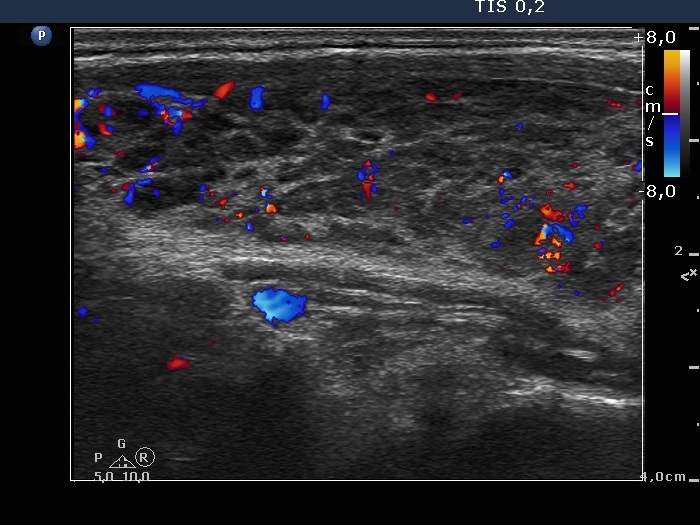

Case 467 (ultrasonographic picture 4)

Right lobe, longitudinal view, color Doppler mode.